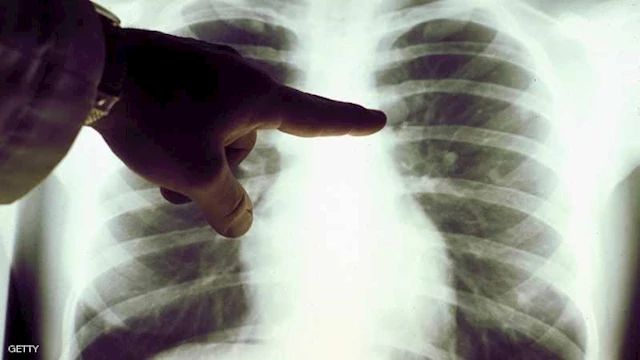

أشارت صحيفة دايلي ميل إلى أن باحثين من جامعة لندن كوليدج وجامعة أكسفورد سيقودون تجربة جديدة تستمر أربع سنوات لبحث لقاح LungVax الوقائي من سرطان الرئة، ومن المتوقع أن تبدأ مرحلتها الأولى في صيف عام 2026. ستتركز المرحلة الأولى على تحديد الجرعة المثلى للقاح وتقييم الآثار الجانبية المحتملة للجرعات المختلفة لدى الأشخاص المعرضين لمخاطر عالية. كما ستسعى التجربة إلى فهم كيفية تفاعل الجهاز المناعي مع المستضدات المرتبطة بخلايا الرئة غير الطبيعية.

سيتم تنفيذ التجربة على مرضى تم تشخيصهم بسرطان الرئة في مرحلة مبكرة وتم استئصال الورم بنجاح، ما يجعلهم عرضة لعودة المرض. وستجرى التجربة ضمن برنامج فحص سرطان الرئة التابع لهيئة الخدمات الصحية الوطنية في إنجلترا، لضمان انخراط من هم في خطر عالٍ. يؤكد الباحثون أن الهدف هو حماية هؤلاء المرضى من عودة المرض عبر اللقاح قبل ظهوره.